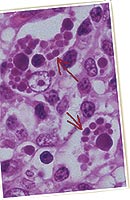

2. Présence de lésions microscopiques caractéristiques dans les organes lymphoïdes : le rapport d’histologie du laboratoire d’analyses mentionne alors une déplétion lymphocytaire avec infiltration histiocytaire (granulomateuse). Il y a une présence variable de cellules géantes multinucléées (au milieu des années 90, ce critère était considéré comme essentiel ; depuis, il n’est que secondaire). La présence d’inclusions intracytoplasmiques est fréquente (si une technique additionnelle est mise en œuvre, il est possible d’observer que ces agrégats contiennent du PCV2).

3. Détection de PCV2 dans les lésions des tissus lymphoïdes typiques (point 2), chez cet animal (point 1), par une technique qui permet d’estimer la quantité de PCV2 (ses protéines, par immunomarquage, ou son génome, par hybridation in situ), et de l’associer à l’intensité des lésions.